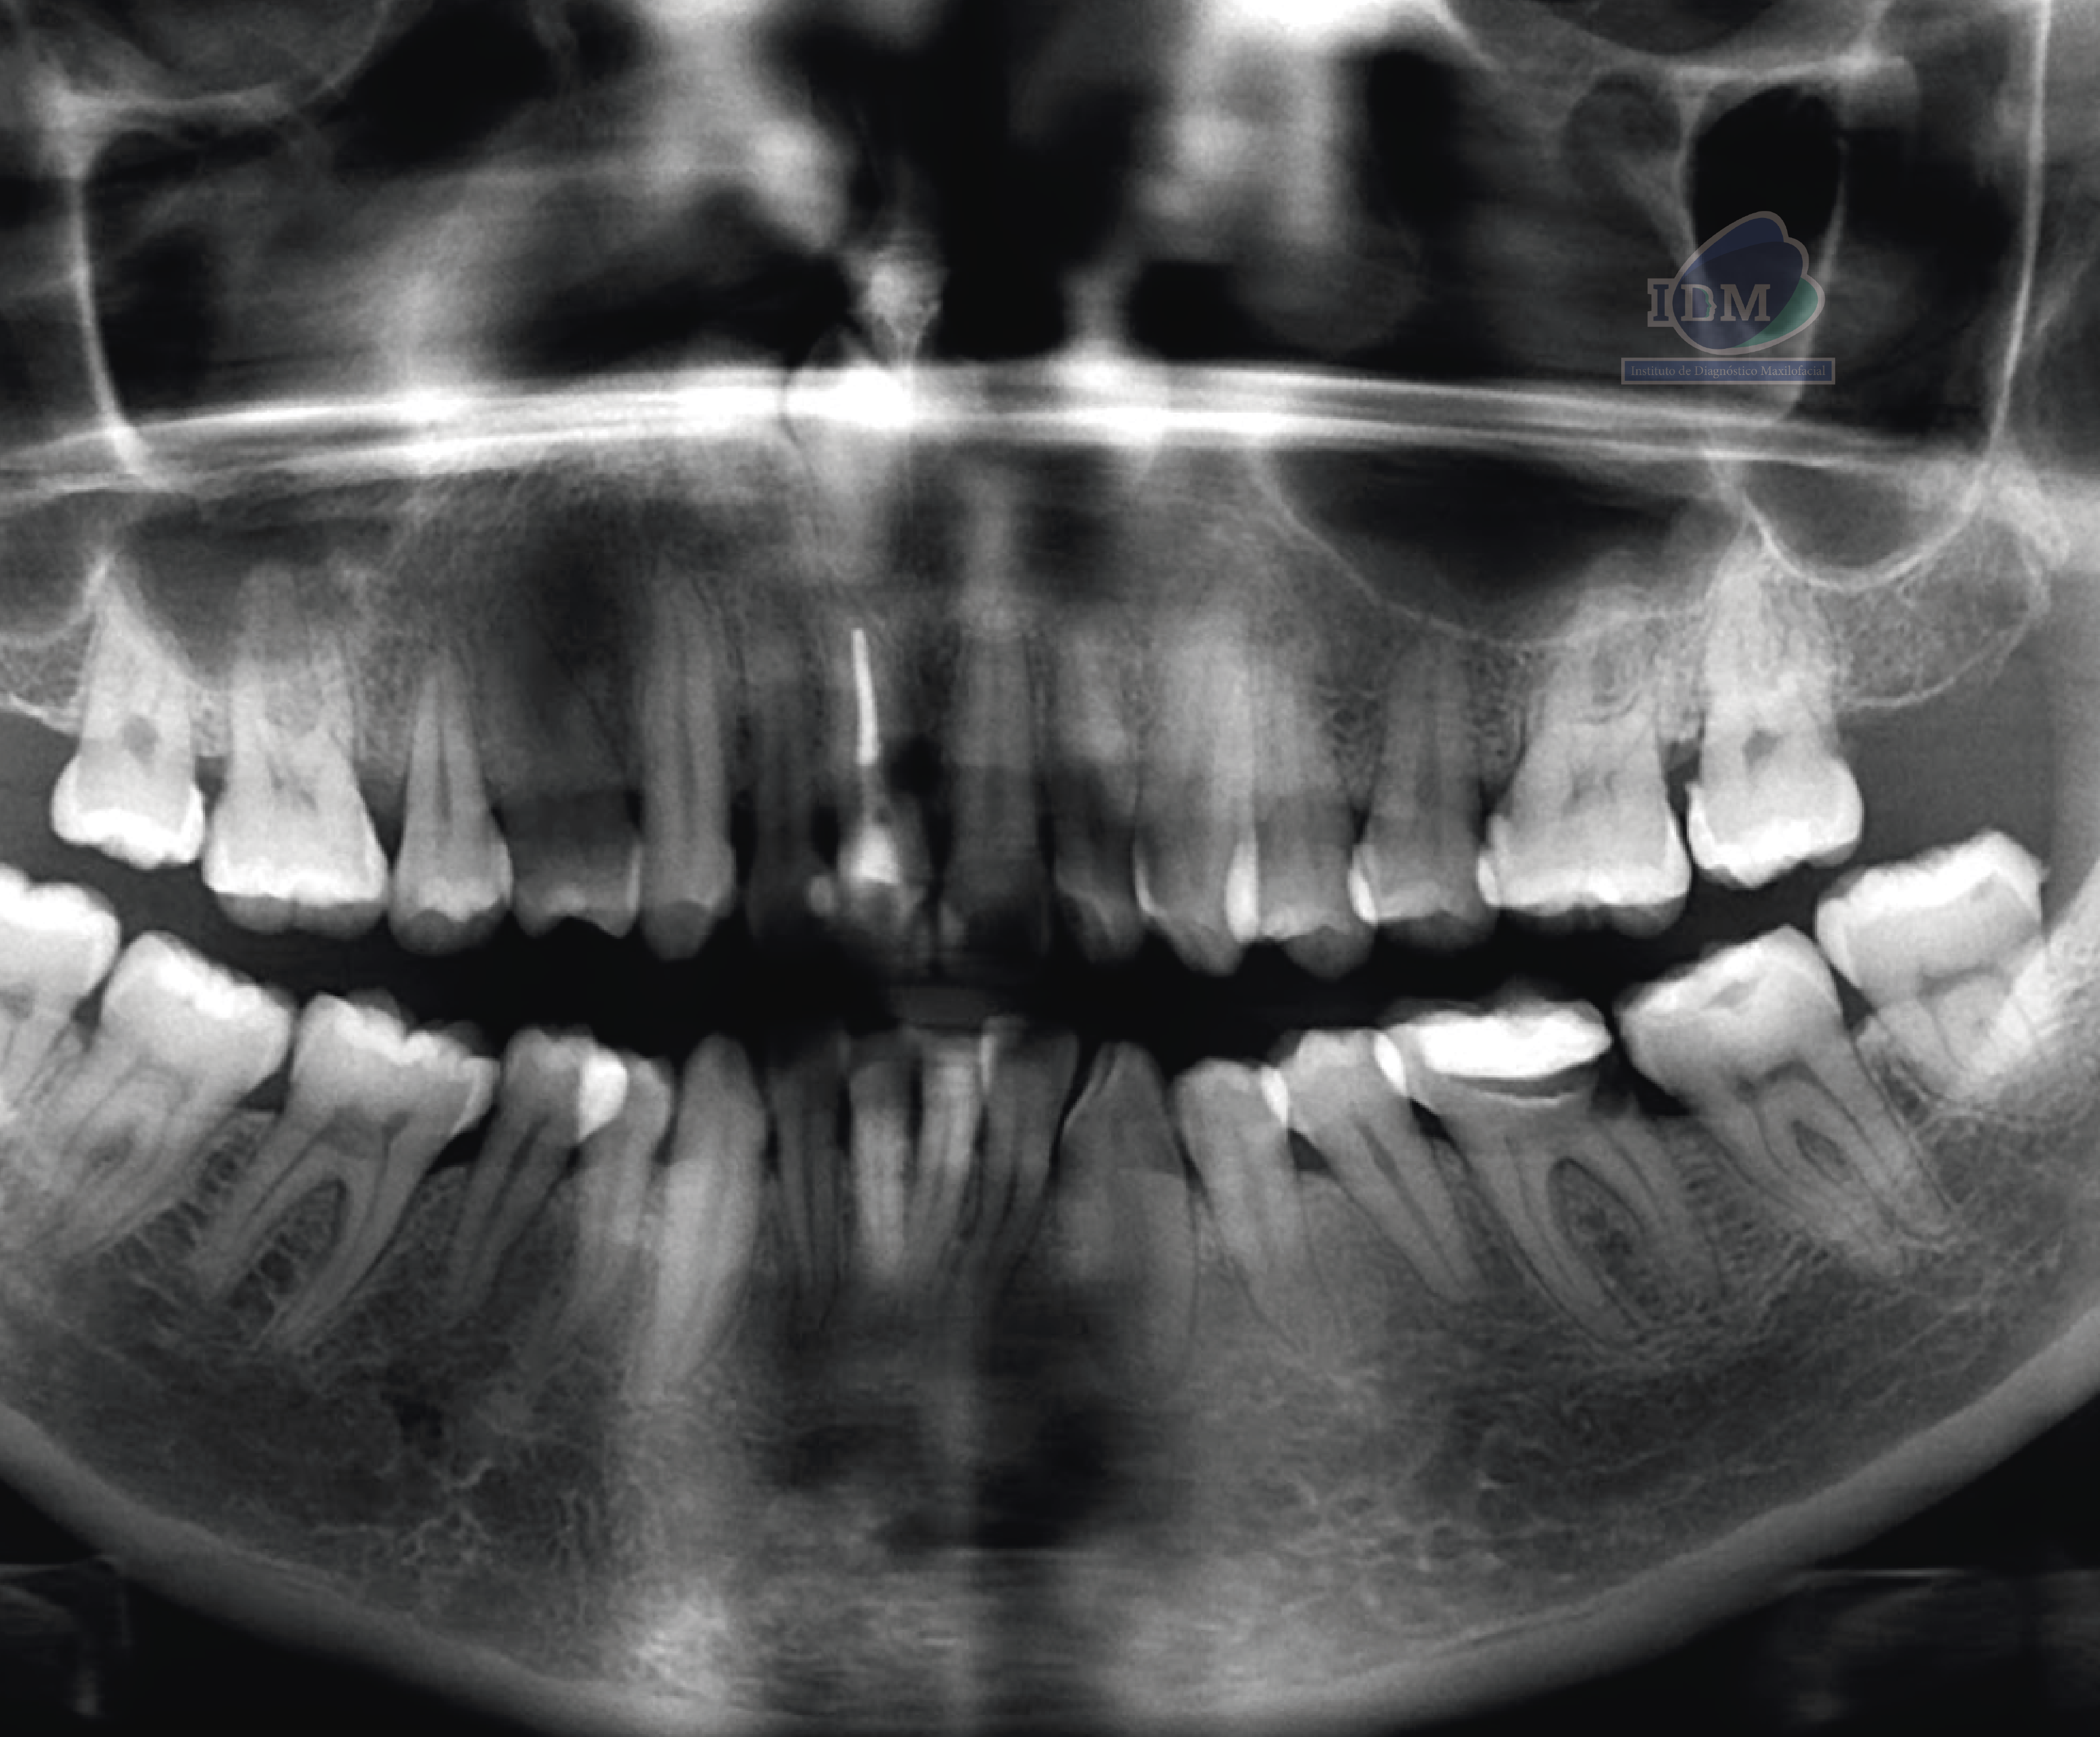

En la radiografía panorámica (Figura 1), se aprecia pieza supernumeraria invertida proyectada en zona anterior del maxilar superior.

Radiografia Panorámica